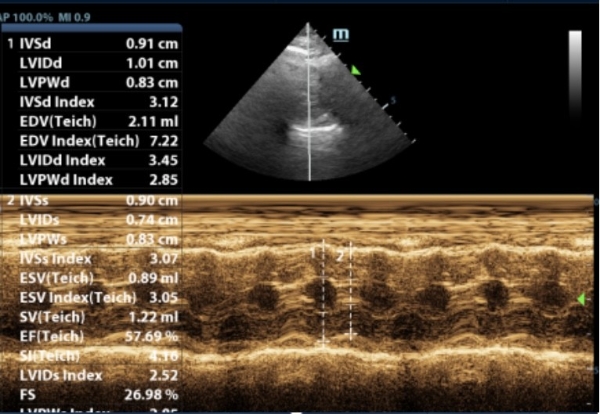

心脏科:精细检测,守护每次心跳

心脏疾病是老年宠物常见的健康问题,医院配备了进口心脏彩超设备,能够精准诊断各种心脏疾病。负责心脏科的张培培医生擅长心肌病、肥厚型心肌病等复杂心血管疾病,并提供长期药物管理和定期随访服务,帮助宠物维持良好的心脏功能。

此前,6岁的猫咪因抽搐呕吐,后腿无力就诊,经查后发现左心室心肌及室间隔厚度增加,主动脉和二尖瓣均存在反流,诊断为肥厚型心肌病。口服利尿剂和抗血栓药物,一周后精神好转,再无出现抽搐、呕吐、后腿无力等现象。